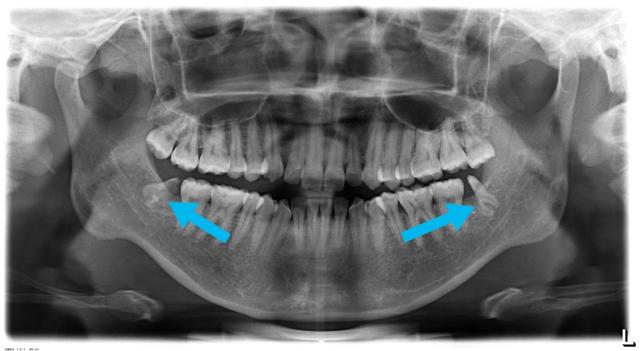

他智点牙根很长,离下牙槽神经很近,我给他拍过口腔ct发现,牙根和神经管之间有一点重叠,牙根与神经管之间没有骨质阻挡,于是我建议他做截冠助萌,等牙齿根离开神经管远一点以后再拔牙齿,这样分两次处理虽然麻烦一点,但是很安全

(绿色箭头指的是下牙槽神经管,黄色箭头指的是牙根,两者有重叠,须加拍cT)